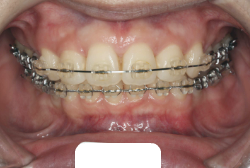

歯科矯正用アンカースクリューを用いた症例(骨格性反対咬合 非抜歯治療)

「ものがうまく噛めない」という主訴で来院したケースです。診断の結果、「骨格性反対咬合に伴う咬合不良+軽度叢生」と判明しました。原因としては特に下顎の左側が過成長したため、骨格性反対咬合になり、特に左側での噛み合わせが非常に悪くなっていると診断しました。初診時の写真を見ると、上下の正中線の大きなズレ、左側の噛み合わせの不良がはっきり分かります(黄色の矢印と緑の矢印は一致しているのが正しい状態です)。

今回の患者様の場合は、「外科」も「小臼歯抜歯」も拒否されましたので、歯科矯正用アンカースクリュー(以下 アンカースクリュー)を用いて、下顎の歯列全体を後方に下げるという方法を取りました。

治療中の写真で、アンカースクリューより歯を後ろへ牽引しているのがお分かりいただけるかと思います。牽引を1年ほど続け、途中補助的に上下にゴムをかける(これを顎間ゴムと言います)手法なども追加し、全体で21ヶ月で治療を終えることが出来ました。

結局歯の本数を減らすことなく、すべてご自分の歯を残して、正しい配列と噛み合わせにすることができました。凸凹があまりひどくないため、簡単そうに見えると思いますが、このケースの初診の状態を見ると、熟練の矯正歯科医でも悩みのつきないケースです。まして、外科も出来ない、抜歯もイヤ、と言うことになると、従来の方法では治療不可能と考えられるのですが、アンカースクリューを使うことで最近は不可能が可能となってきました。